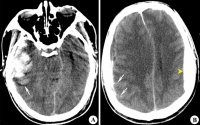

外伤性进展性颅内出血病变

右额颞叶脑挫裂伤合并蛛网膜出血

伤中,首次CT的阳性发现率竟占18%,并有5%需行手术治疗,强调早期CT检查的必要性。

对脑挫裂伤与脑震荡可以作出明确的鉴别诊断,并能清楚地显示脑挫裂伤的部位、程度和有无继发损害,如出血和水肿情况。同时,可根据脑室和脑池的大小、形态和移位的情况间接估计颅内压的高低。尤为重要的是,对一些不典型的病例,可以通过定期CT扫描,动态地观察脑水肿的演变或迟发性血肿的发生。近年来,在有此设备的医院CT已作为急性头伤的常规检查,因为单靠伤史和查体难以作出超早期诊断。Stein等(1990)指出在GCS13~15危害较小的轻型头